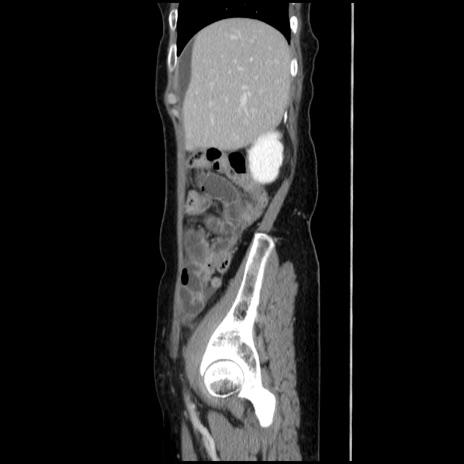

冠状断像